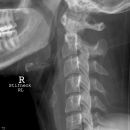

Foramen arcuale bzw Kimmerle Anomalie